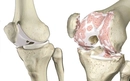

Sağ Diz Kapağı Ağrısı: Belirtileri ve TedavisiDiz kapağı, vücudun en karmaşık eklemlerinden biri olup, günlük yaşamda önemli bir rol oynamaktadır. Sağ diz kapağında meydana gelen ağrı, birçok insanda yaygın bir sorundur ve çeşitli nedenlerden kaynaklanabilir. Bu makalede, sağ diz kapağı ağrısının belirtileri, olası nedenleri ve tedavi yöntemleri detaylı bir şekilde ele alınacaktır. BelirtilerSağ diz kapağı ağrısının belirtileri kişiden kişiye değişiklik gösterebilir. Ancak genellikle aşağıdaki belirtiler gözlemlenmektedir:

NedenlerSağ diz kapağı ağrısının birçok olası nedeni bulunmaktadır. Bu nedenler arasında şunlar yer alır:

Tanı YöntemleriSağ diz kapağı ağrısının doğru bir şekilde tanımlanması için çeşitli tanı yöntemleri kullanılmaktadır. Bu yöntemler şunlardır:

Tedavi YöntemleriSağ diz kapağı ağrısının tedavi yöntemleri, ağrının nedenine bağlı olarak değişiklik göstermektedir. Tedavi yöntemleri arasında: